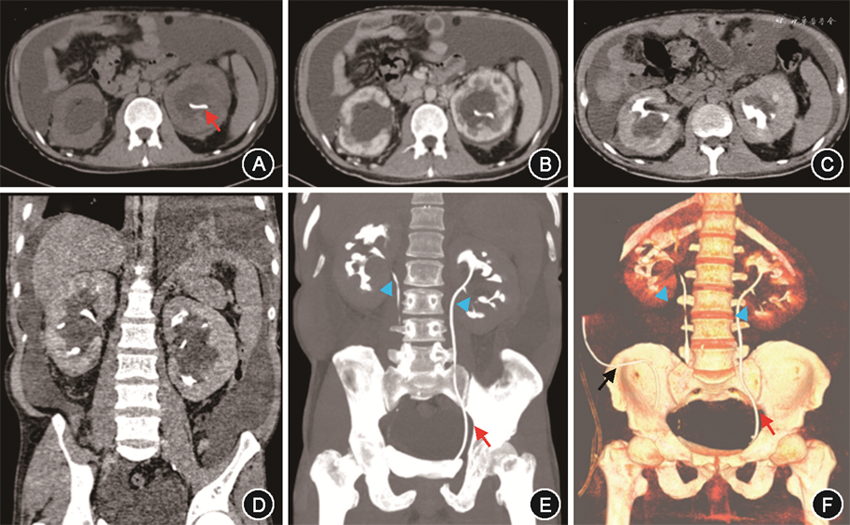

入院后实验室检查:Hb 134 g/L,白细胞(WBC)11.42×109/L,血小板528×109/L。血生化:Alb 29 g/L,丙氨酸转氨酶 106 U/L,天冬氨酸转氨酶 60 U/L,碱性磷酸酶677 U/L,谷氨酰胺转移酶 334 U/L,总胆红素12.4 μmol/L,磷1.8 mmol/L,钙2.24 mmol/L,SCr 138 μmol/L。超敏C反应蛋白(hsCRP)>250 mg/L,红细胞沉降率(ESR)86 mm/1h,白细胞介素(IL)-6 104.0 ng/L,IL-8 68.0 ng/L,肿瘤坏死因子(TNF)-α 17.3 ng/L,血管内皮生长因子(VEGF)270.0 ng/L。外周血抗PLA2R:阴性。血清蛋白电泳、免疫固定电泳、自身免疫性疾病及感染指标均阴性。24 h尿蛋白0.4 g。腹水常规:WBC 92×106/L,单核细胞 73×106/L,黎氏试验(-)。腹水生化:总蛋白 5 g/L,Alb 4 g/L(同期血清Alb 30 g/L),腺苷脱氢酶 0.6 U/L,乳酸脱氢酶 44 U/L,葡萄糖 5.0 mmol/L。病原学、肿瘤标志物、肿瘤细胞:阴性。超声:双侧锁骨上窝及颈部多发肿大淋巴结,皮髓质分布不清,较大者位于右侧锁骨上窝(1.9 cm×1.3 cm)。泌尿系超声:双肾盂无回声,内见分隔,符合肾盂周囊肿。心脏超声:未见明显异常。CT尿路造影:双肾盂周围低密度灶,肾盂周囊肿可能;双肾体积增大,密度、强化不均,双肾周可见积液包绕;左侧D-J管置入术后;多浆膜腔积液;门静脉系统未见血栓(图1)。淋巴显像:肾实质弥漫性淋巴管扩张;双下肢内侧集合淋巴管、左静脉角淋巴管扩张可能;双肾盂囊肿占位,肾周低密度影,腹腔见大量积液。尿乳糜试验、腹水乳糜试验均阴性。肾脏穿刺病理本院会诊:符合膜性肾病,合并肾小管间质病变。病理结果:(右侧锁骨上淋巴结)符合Castleman病(透明血管型)(图2)。因患者尿蛋白量少,提示膜性肾病非复发状态,膜性肾病无法解释患者反复肾周出血、双肾盂周囊肿,且患者合并大量腹水,行肾脏穿刺难度大、出血风险高,故未行重复肾活检。治疗方面予间断引流腹水(共计约12 000 ml)、补充白蛋白、呋塞米+螺内酯联合利尿,胸闷、憋气、干咳症状好转,拔除引流管,体重稳定于55 kg左右,腹围82 cm,脉搏70~80 次/min,不吸氧状态下动脉血氧饱和度96 %。复查hsCRP 5.7 mg/L,IL-6 15.4 ng/L,IL-8 16.0 ng/L,IL-10 5.0 ng/L,TNF-α 15.9 ng/L,血清Alb 36 g/L,SCr 101 μmol/L,胸腹盆CT示胸水及腹水明显减少。经内科大查房(消化科、肾内科、血液科、放射科、核医学科、病理科)讨论,考虑特发性多中心Castleman病(iMCD)诊断明确,目前已无疾病活动证据,建议随诊观察,若再出现疾病活动表现,可针对iMCD治疗;患者膜性肾病病情稳定,监测血清Alb、SCr好转,且患者对肾脏穿刺并发症顾虑较大,遂未重复肾活检,建议定期监测肾功能、24 h尿蛋白。因iMCD难以解释反复肾周出血,需警惕肾盂周囊肿导致肾静脉压力升高继发出血可能,建议规律利尿、定期监测泌尿系影像学。出院随访至2021年10月29日,病情稳定。

注:红色箭头示左侧D-J管;蓝色三角示肾盂受压狭窄处;黑色箭头示腹腔引流管